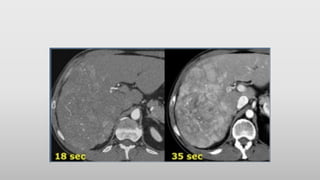

• The CT-images show an early arterial phase in comparison to a late arterial

phase.

• The CT-images are of a patient who underwent two phases of arterial

imaging at 18 and 35 seconds.

In the early arterial phase we nicely see the arteries, but we only see some

irregular enhancement within the liver.

In the late arterial phase we can clearly identify multiple tumor masses.

• For late arterial phase imaging 35 sec is the optimal time, so you start at

about 25 seconds and end at about 45 seconds.

However if you have a 64-slice scanner, you will be able to examine the

whole liver in 4 seconds. So you start scanning at about 33 seconds, which

is much later.

In arterial phase imaging the time window is narrow, since you have only

limited time before the surrounding liver will start to enhance and obscure

a hypervascular lesion.